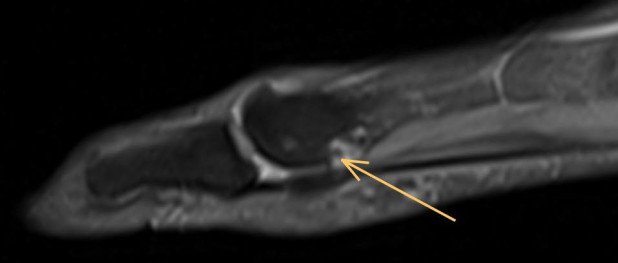

Fragliche Darstellung des Überbeines im MRI

Zur genaueren Untersuchung und Darstellung machten wir daher ein CT, das die Knochen besser darstellt.